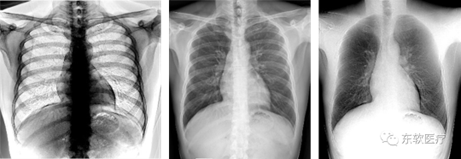

● 双能骨肉分离成像

「北斗」创新的双能成像技术,通过算法对高、低能成像进行重建,获得单纯骨组织和软组织图像,实现“骨肉分离”,有效提升肺部病灶或肋骨骨折等疾病的检出能力。

骨骼图像 | 融合图像 | 软组织图像